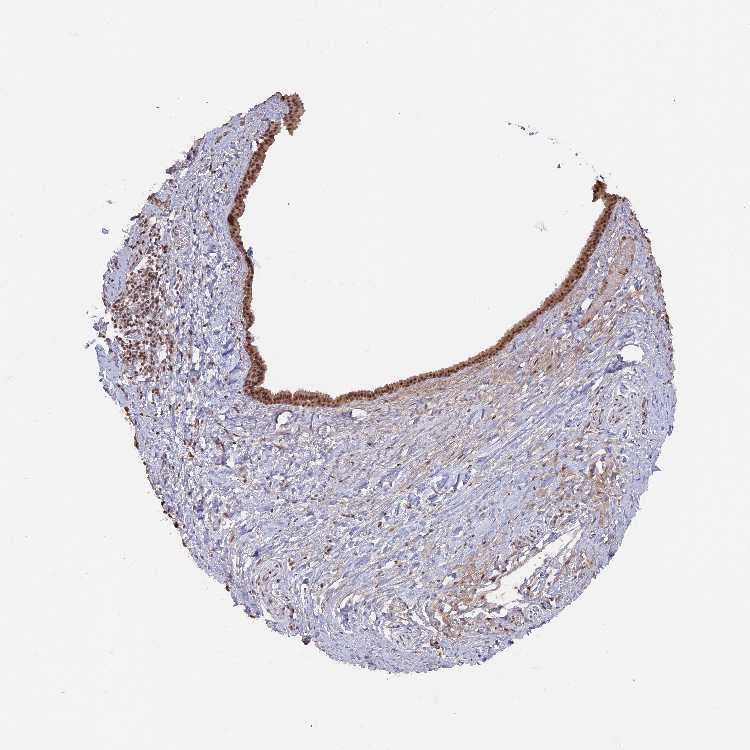

SOFT TISSUE 1 - Antibody stainingi

Antibody staining in the annotated cell types in the current human tissue is reported as not detected, low, medium, or high, based on conventional immunohistochemistry profiling in selected tissues. This score is based on the combination of the staining intensity and fraction of stained cells.

Each image is clickable and will lead to virtual microscopy that enables deeper exploration of all samples and also displays staining intensity scores, fraction scores and subcellular localization as well as patient and tissue information for each sample.

Antibody HPA042843Antibody HPA049439

Chondrocytes HighNot detected

Fibroblasts MediumMedium

Peripheral nerve Medium-

SOFT TISSUE 2 - Antibody stainingi

Antibody HPA042843

Chondrocytes High

Fibroblasts Medium